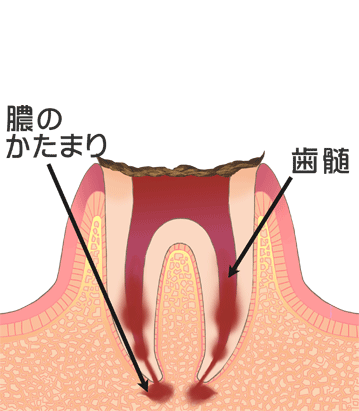

⑥ 前回詰めた綿花の状態を確認して、良い状態なら、「根管充填剤」(マスターポイント・アクセサリーポイント)というお薬を、余分な空間がないように根っこに詰めます。

⑥ 前回詰めた綿花の状態を確認して、良い状態なら、「根管充填剤」(マスターポイント・アクセサリーポイント)というお薬を、余分な空間がないように根っこに詰めます。 Q1.痛みはありますか?

Q1.痛みはありますか? ② 次に、「根管長測定器」という機械を使い、根っこの長さを正確に測ります。

② 次に、「根管長測定器」という機械を使い、根っこの長さを正確に測ります。

⑤ 次に、仮詰めをします。 虫歯が神経まで達して炎症を起こしているので、人によってはズキズキとした痛みを感じる方もいます(>_<)

虫歯が神経まで達して炎症を起こしているので、人によってはズキズキとした痛みを感じる方もいます(>_<)